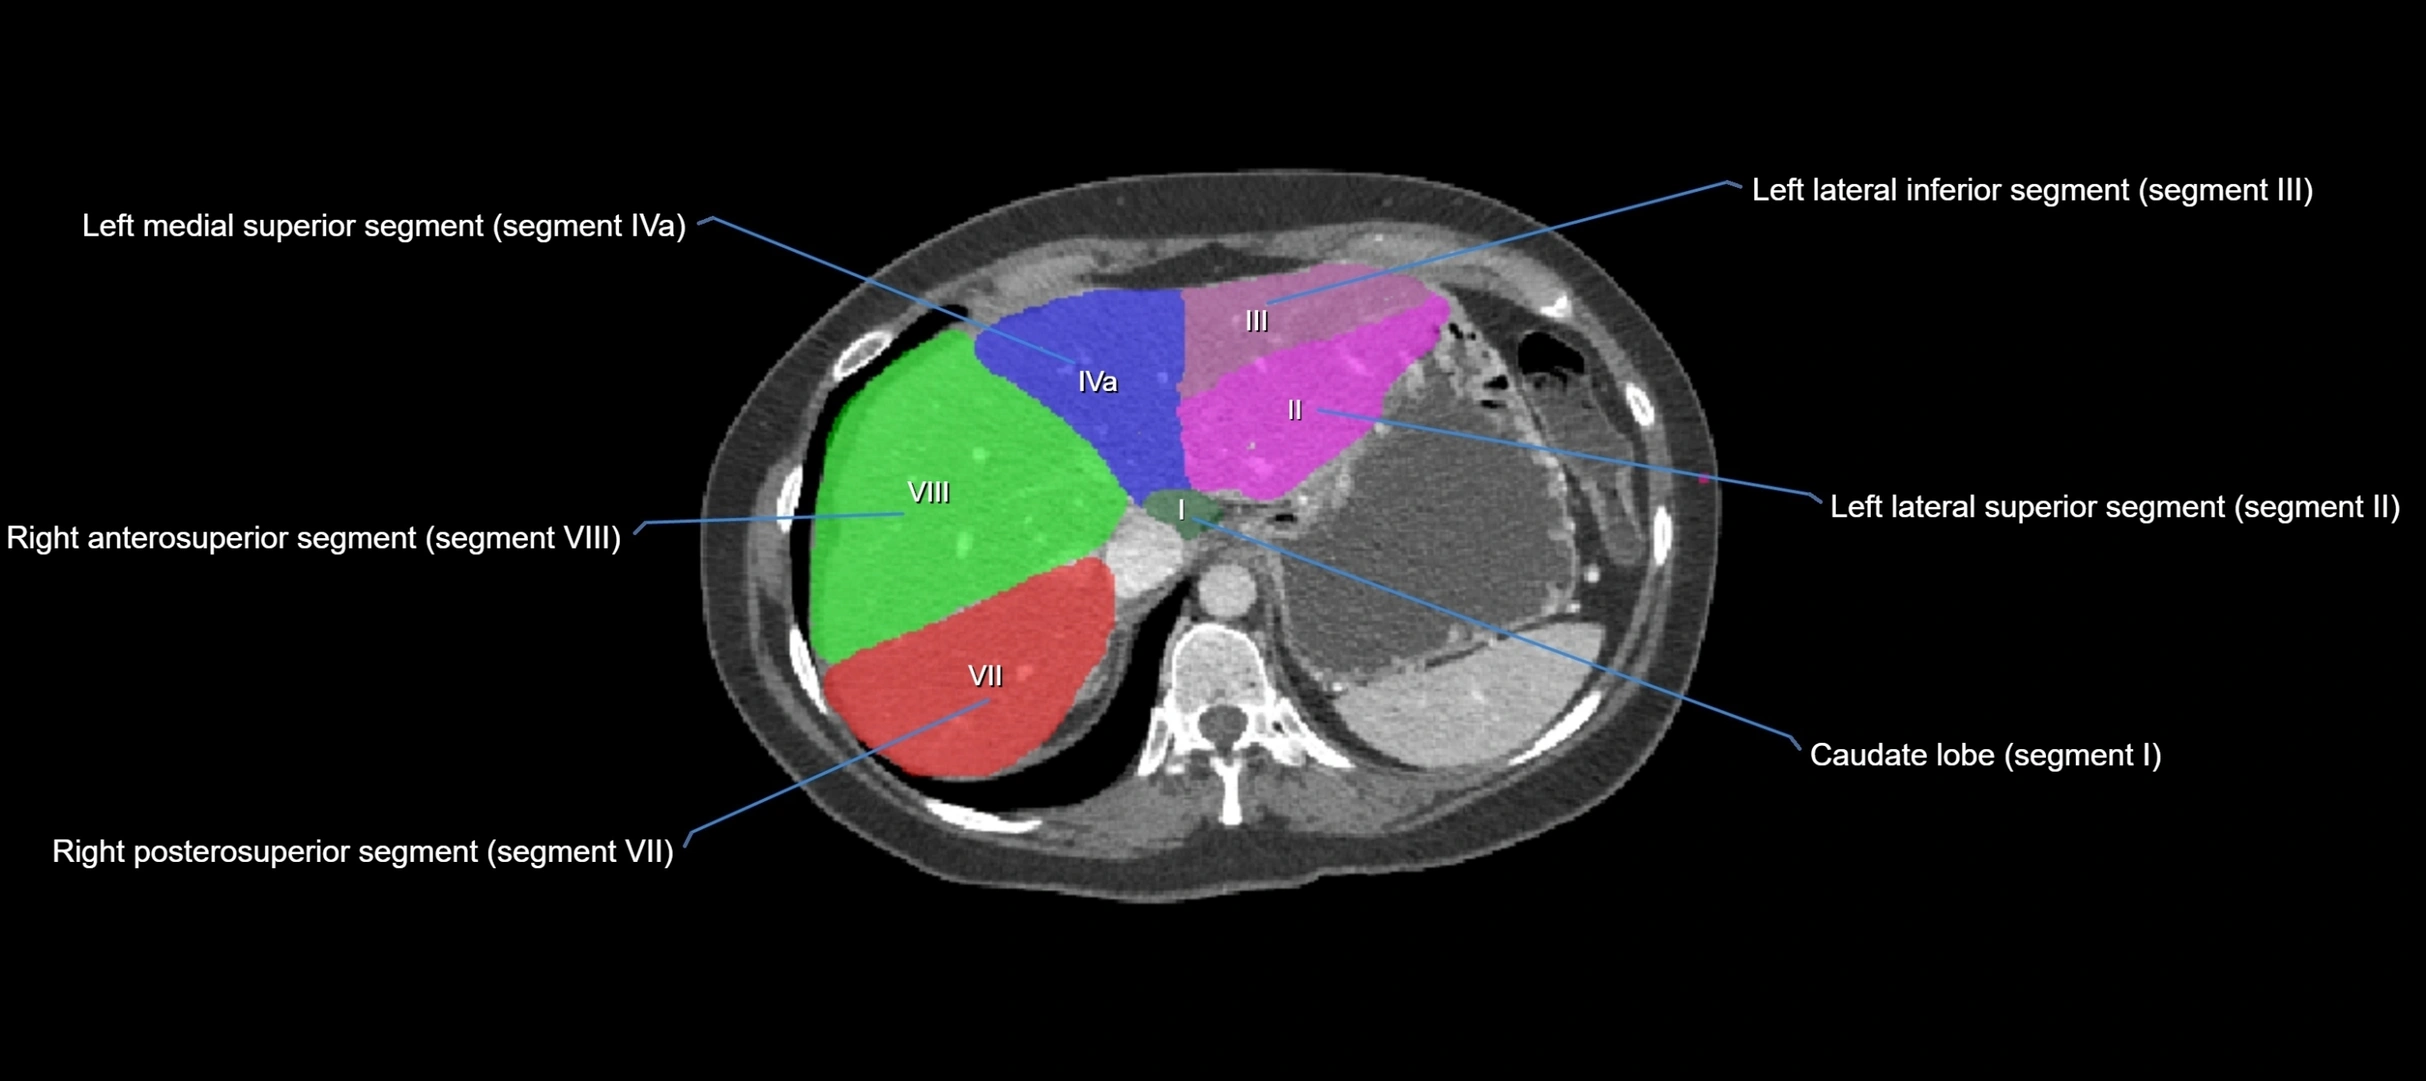

CT Image

image